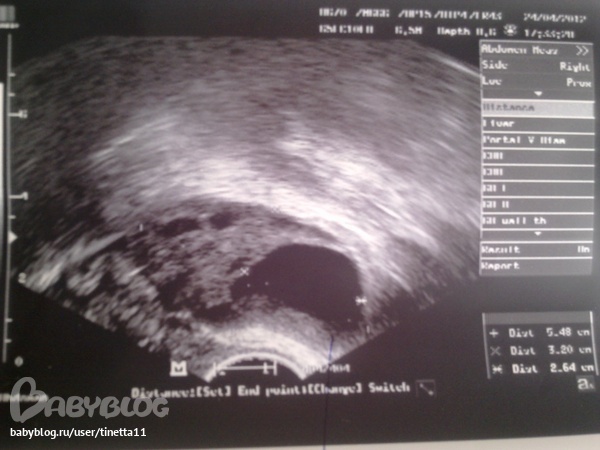

Сегодня 28 день цикла, решила для интереса сходить на узи, а там непонятная картина.....

Узистка сказала, что не понятно, что это, фолликул или желтое тело....

Как вы думаете, что это? посмотрите картинку......

Размер этого "непонятного образования" в яичнике 20 на 26мм

Татьяна, ранее у Вас не было О , т.к. Утрик пьется только после подтвержденной О. У меня ДФ из-за того, что я пила Дюф раньше произошедшей О переростал в кисту. А у меня наоброт в этом Ц подтвердили О, на снимке узистка сказала , что точно желтое тело, и температура так же не поднимается. Если не ошибаюсь на снимке ДФ или киста темного цвета с четкими границами, а желтое тело с неровным краями.

Доброе утро, Виктория! Так в том то и дело, что я ходила на фолликулометрию начиная с 7 дня цикла, ходила на 7,11,16 – на 16 было понятно, что ничего не растет, т.к. в левом яичнике(как раз тот, что на картинке) был самый большой фоллик 11мм. И тут я ради интереса пришла на 28 день цикла, а там вот это, что-то непонятное…Ну думаю опять киста, т.к. базальная температура не поднялась, а даже наоборот, начиная с 17 дня цикла стала ниже чем до до него….

И тут я решила в этом уикле не пить утрожестан без подтвержденной овуляции....,ходила-ходила на узи, на 16день цикла максимальный фоллик был 11мм(кстати в этом же яичнике, что и на картинке)...,мне сказали, что овуляции не будет...,ну я и решила не пить Утрожестан, пришла сегодня(на 28 день цикла) на узи, а там вот это, непонятное образование...(толи фоллик, толи желтое тело, толи еще что-то....)

Вообще по форме на ЖТ больше похоже, но у меня на фото с узи оно почему то другого цвета немножко.

Скорей ЖТ, фоллик правильной круглый ну или овальный, но округлый короче-))) а с неровными краями как раз ЖТ.